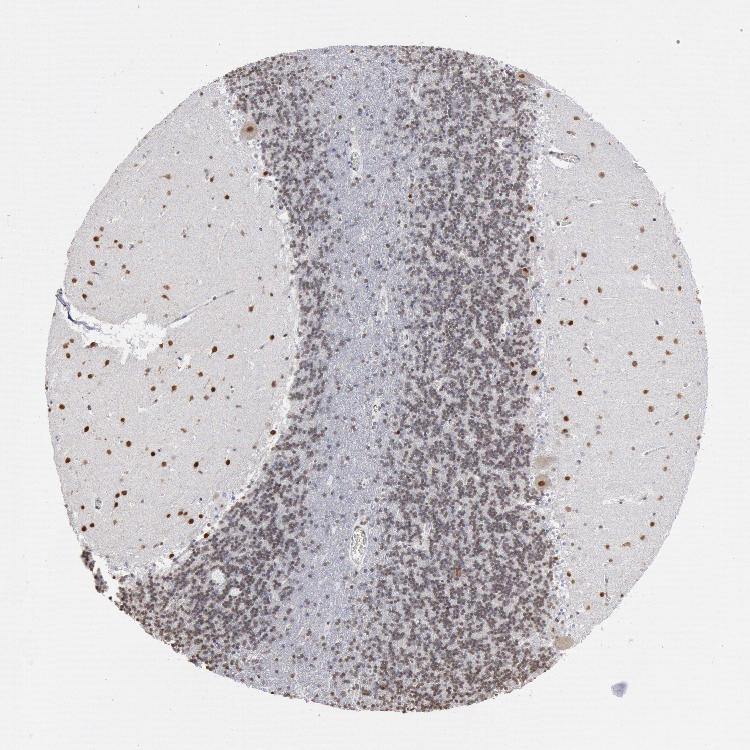

CEREBELLUM - Antibody stainingi

Antibody staining in the annotated cell types in the current human tissue is reported as not detected, low, medium, or high, based on conventional immunohistochemistry profiling in selected tissues. This score is based on the combination of the staining intensity and fraction of stained cells.

Each image is clickable and will lead to virtual microscopy that enables deeper exploration of all samples and also displays staining intensity scores, fraction scores and subcellular localization as well as patient and tissue information for each sample.

Antibody HPA001311Antibody CAB015351

Purkinje cells HighHigh

Cells in granular layer MediumMedium

Cells in molecular layer HighHigh